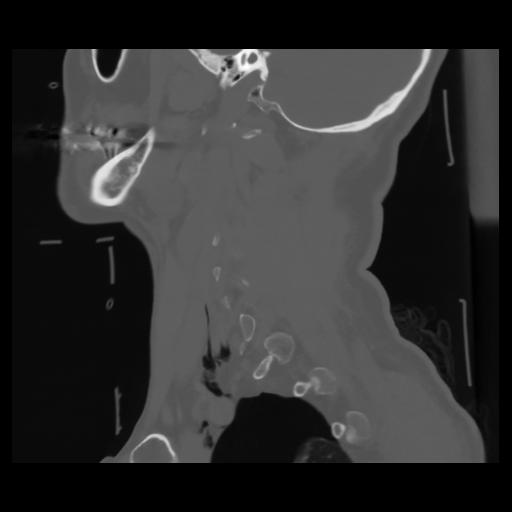

14 P.BLANDAS,,Sagittal,2.000,P.BLANDAS,Sagittal,